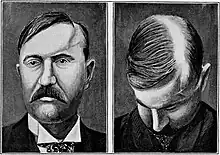

| a 17-year-old girl with Parry–Romberg syndrome. The subcutaneous tissue and underlying facial muscles on the right side of the face are severely atrophic, while the left side is unaffected. | |

Parry–Romberg syndrome (PRS) is a rare disease characterized by progressive shrinkage and degeneration of the tissues beneath the skin, usually on only one side of the face (hemifacial atrophy) but occasionally extending to other parts of the body.[1] An autoimmune mechanism is suspected, and the syndrome may be a variant of localized scleroderma, but the precise cause and pathogenesis of this acquired disorder remains unknown. It has been reported in the literature as a possible consequence of sympathectomy. The syndrome has a higher prevalence in females and typically appears between 5 and 15 years of age.

Initial facial changes usually involve the area of the face covered by the temporal or buccinator muscles. The disease progressively spreads from the initial location, resulting in atrophy of the skin and its adnexa, as well as underlying subcutaneous structures such as connective tissue, (fat, fascia, cartilage, bones) and/or muscles of one side of the face.[2] The mouth and nose are typically deviated towards the affected side of the face.[3]

The process may eventually extend to involve tissues between the nose and the upper corner of the lip, the upper jaw, the angle of the mouth, the area around the eye and brow, the ear, and/or the neck.[2][3] The syndrome often begins with a circumscribed patch of scleroderma in the frontal region of the scalp which is associated with a loss of hair and the appearance of a depressed linear scar extending down through the midface on the affected side. This scar is referred to as a "coup de sabre" lesion because it resembles the scar of a wound made by a sabre, and is indistinguishable from the scar observed in frontal linear scleroderma.[4][5]

In 20% of cases, the hair and skin overlying affected areas may become hyperpigmented or hypopigmented with patches of unpigmented skin. In up to 20% of cases the disease may involve the ipsilateral (on the same side) or contralateral (on the opposite side) neck, trunk, arm, or leg.[6] The cartilage of the nose, ear and larynx can be involved. The disease has been reported to affect both sides of the face in 5 to 10% of cases.[4]